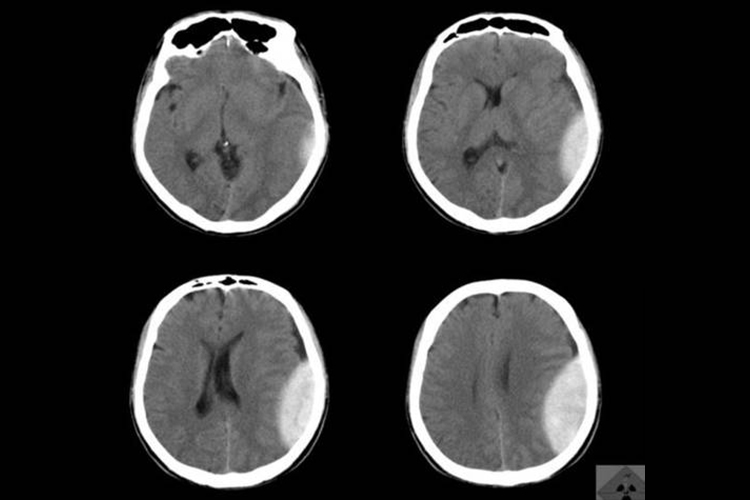

左侧硬膜下血肿是因血液淤积在左侧硬脑膜下腔形成的多发性血肿,CT可见高密度影像或点状出血灶,还可伴有头晕、呕吐等症状。

左侧急性硬膜下血肿CT检查示颅骨内板与脑组织表面之间有高密度、等密度或混合密度的新月形或半月形影;慢性硬膜下血肿CT检查示颅骨内板下低密度的新月形、半月形或双凸镜形影,还可出现中线移位、脑室受压的情况。